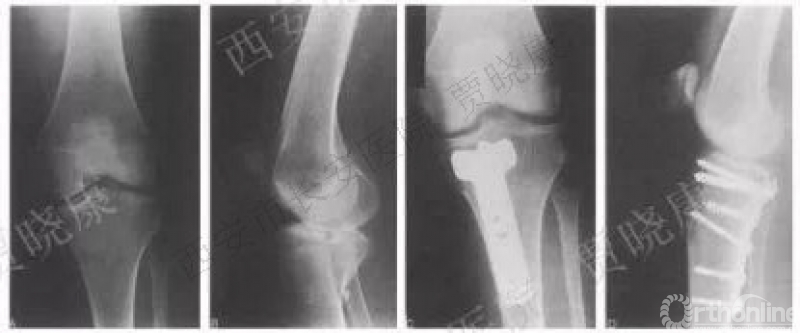

2. Carlson后外侧入路

2005年

该方法:为后侧2个弧形切口、便于显露后内、后外。适用于41B2.3x或w、41B3.2x或w、41B1可41B2.1x或u。

原文:8例患者有后双髁胫骨平台骨折。2名患者有抑郁后外侧胫骨平台骨折中的缺陷并没有直接暴露骨折部位。1人死于医疗问题导致5例直接骨折暴露、复位、固定。

4.后外侧入路

2009年俞光荣

该方法:直接暴露。适用于41B2.1x或u、41B3.1x或u.

原文:8例中年患者后外侧冠状动脉骨折的胫骨外侧平台。8例患者均行直接骨折暴露、可视化复位、后外侧入路钢板内固定。